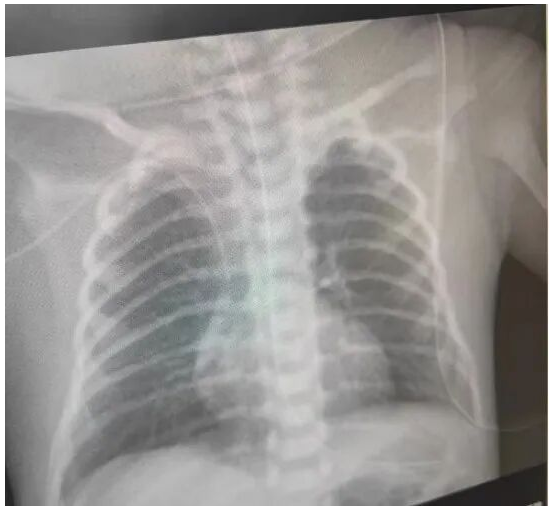

谢新权科室:儿科

职称:副主任医师 -

张晓庆科室:儿科

职称:主任医师 -